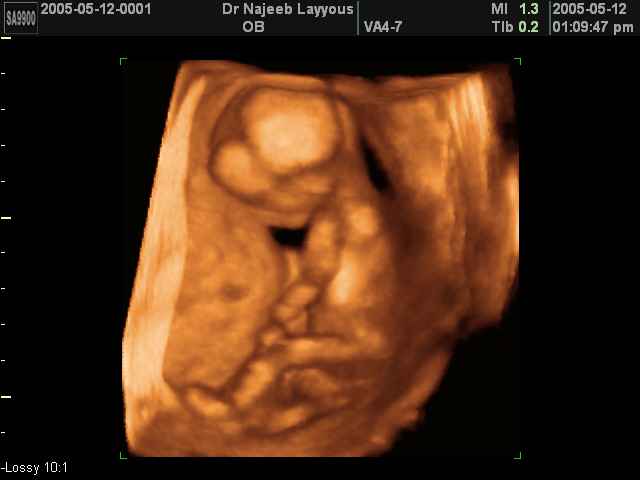

3D First Trimester Ultrasound Scan Photos